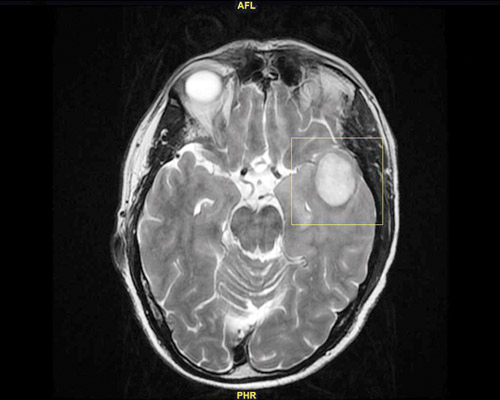

هذا ما أوضحه الدكتور هاني عبد العزيز استشاري جراحة المخ والأعصاب، والذي أضاف أن المريض وصل المستشفى في حالة متأخرة وبعد أن تمكن منه المرض، حيث تم إخضاعه للفحوصات المخبرية الدقيقة والأشعة بالرنين مغناطيسي (M.R.I.)، وقد أبانت النتائج وجود ورم في الفص الصدغي مسبباً إزاحة وضغط كبير على مراكز النطق بالمخ.

على أثر ذلك قام الفريق الطبي بدراسة نتائج الفحوصات ووضع المريض الصحي جيداً، لافتاً إلى أن العملية تعد واحدة من الجراحات الدقيقة جداً والتي استغرقت 8 ساعات متواصلة، حيث تم استخدام تقنية الميكروسكوب الجراحي المتطور (Pentero)، وجهاز (Sonopet) الذي يعمل على استئصال الأورام في المناطق بالغة الحساسية وتفتيتها دون التأثير على الأنسجة الحيوية بالمخ الملاصقة للورم.